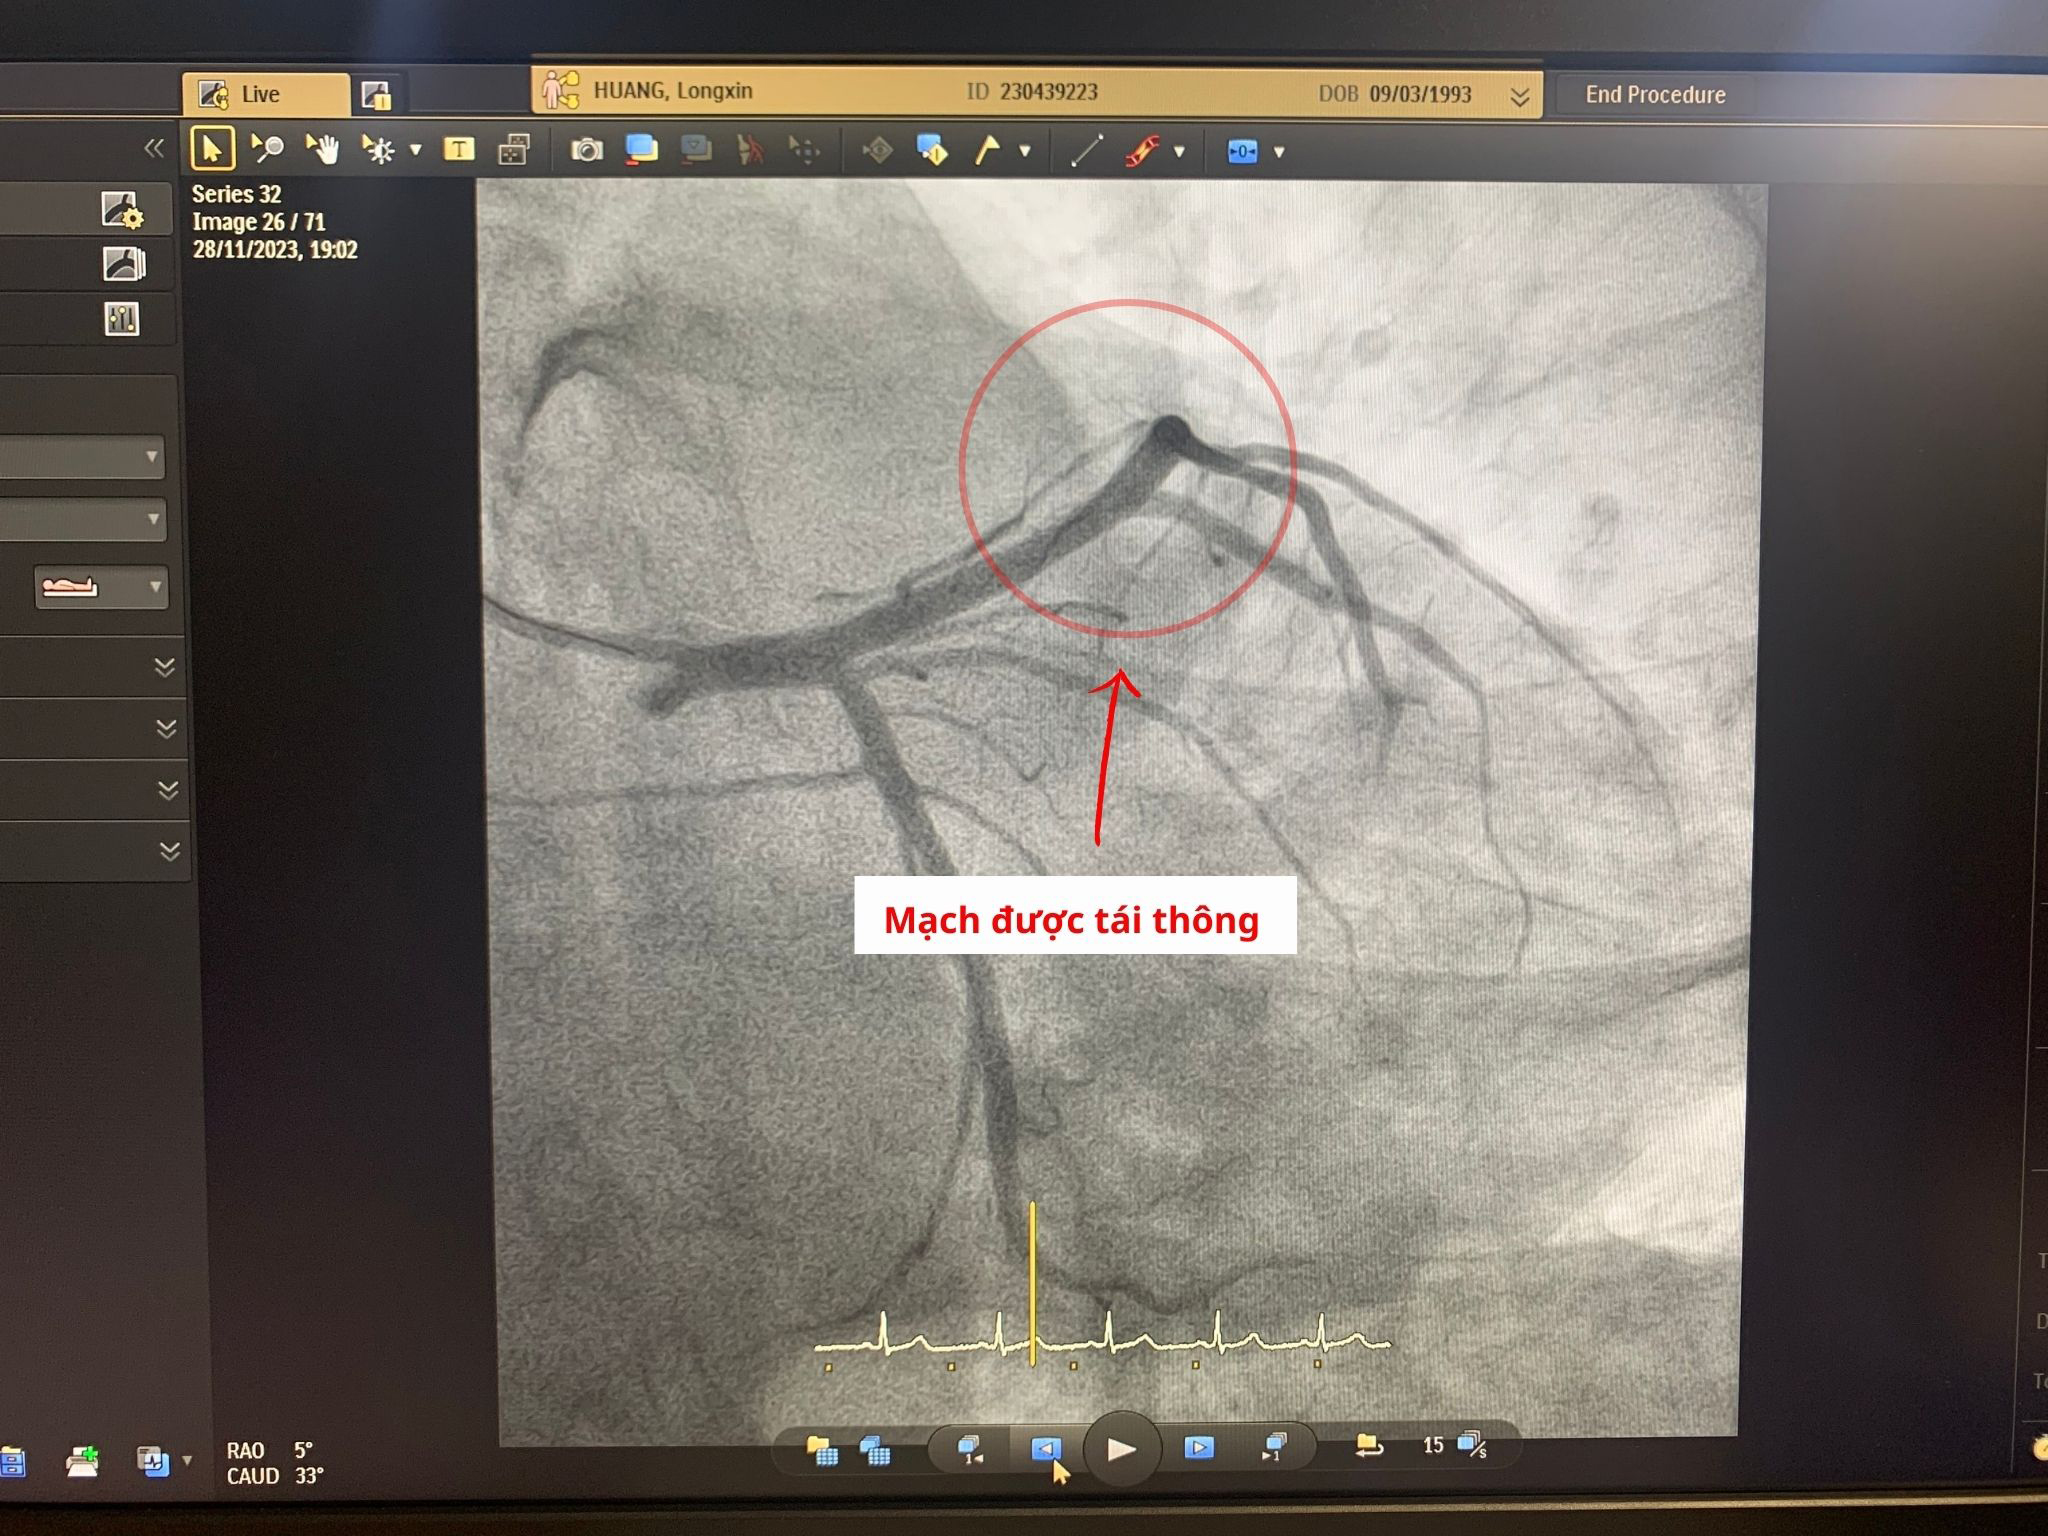

Rất nhanh chóng, ekip bác sĩ tiến hành tái thông động mạch bị tắc bằng cách hút huyết khối, nong bóng tổn thương và đặt stent kích thước 3.5 x 38 (mm). Nhờ can thiệp nhanh, kịp thời nên giảm thiểu tổn thương tế bào cơ tim, tránh được những rủi ro như rối loạn nhịp, suy tim... Sau 24h can thiệp, bệnh nhân hồi phục sức khỏe tốt, không còn các triệu chứng đau tức ngực, chóng mặt, khó thở.

Đoạn mạch bị tắc được tiến hành tái thông và đặt stent kích thước 3.5 x 38 (mm)